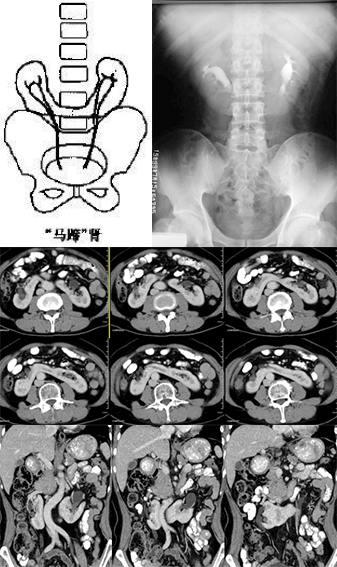

肾形态异常

肾形态异常包括融合肾和分叶肾、驼峰肾和肾柱排列异常

融合肾:指两肾的联合,但每一肾各自具有自已的收集系统和排泄系统

马蹄肾: 是融合肾中最常见的一种, 指两肾的上极或下极相融合,常见下极融合,融合的部分称峡部,由肾实质或结缔组织构成

IVP:两肾下极斜向内侧;两肾盂位置低,且靠近,旋转不良。可伴有肾盂积水